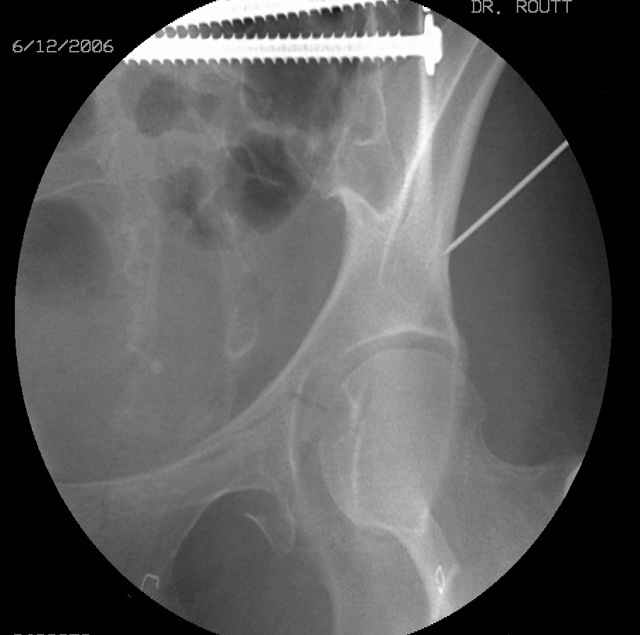

Screw Fixation

-AC Screw

-PC Screw

For Alex... here are some cannulated and 7mm screws for you... notice the fracture malreduction as indicated by the head subluxation on both views...this was a percutaneous technique without open reduction... I don¹t like it but there it is... the fixation technique is not at fault, because there was no open reduction of the fracture... but let¹s not get in to all that.